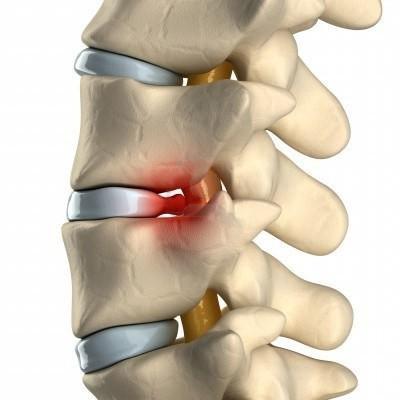

Также причиной часто является шейный спондилез. Это хроническое дегенеративное заболевание возникает из-за повреждения межпозвоночных дисков шеи. Со временем они истончаются, и в итоге возникает межпозвоночная грыжа. Болит при этом шея и голова, приступ острый, очень сильный, локализуется справа или слева.

Главный источник болевых ощущений во время остеоартроза — это повреждённые межпозвонковые суставы. Изменения форм собственных межпозвонковых суставов являются главной причиной острой кривошеи и миофасциальной боли. Грыжи межпозвонковых дисков чаще всего возникают в нижнешейном позвоночном отделе: как правило, повреждаются межпозвонковые диски C5 и C6.

Развитие грыжи межпозвонкового диска чаще всего вызывает болевые ощущения в плече. Передавливание нервного окончания вызывает боли в руке и в плече (брахиалгия). Грыжа позвоночника может создавать нарушения в работе нерва, включающее снижение мышечной силы, чувствительности и рефлекторной активности.

Межпозвоночная грыжа

Вытекая через трещины фиброзного кольца в позвоночный канал, пульпозное ядро оказывает давление на нервные корешки, вызывая тем самым мучительные боли.

Боль локализуется в шее, плече и руке. Характеризуется как острая, становится интенсивнее при повороте головы, чихании, кашле. Болит шея и плечо меньше при заведении руки за голову.